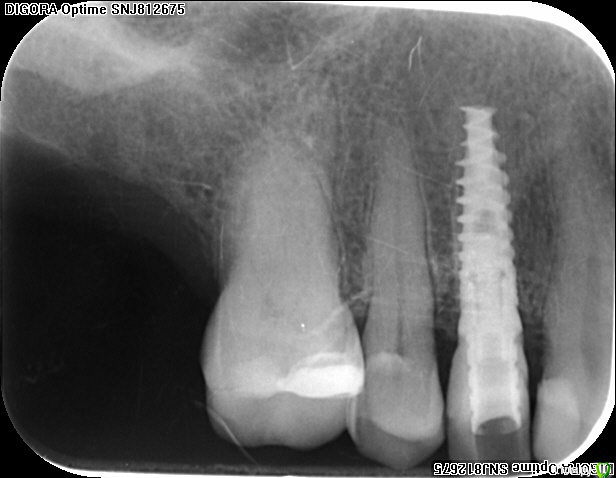

an_ver Опубликовано 14 декабря, 2015 Автор Поделиться Опубликовано 14 декабря, 2015 Абатмент недокручен?Антон, так лучше? 1 Ссылка на комментарий

АнтонТЛТ Опубликовано 14 декабря, 2015 Поделиться Опубликовано 14 декабря, 2015 (изменено) Конечно Ремоделировка что ли началась?))) Изменено 14 декабря, 2015 пользователем АнтонТЛТ Ссылка на комментарий

an_ver Опубликовано 14 декабря, 2015 Автор Поделиться Опубликовано 14 декабря, 2015 Конечно Ремоделировка что ли началась?)))Это та пациентка что абатмент недосаженный был. Вспомнил что надо отчитаться,что не закрутил такой)) Ссылка на комментарий